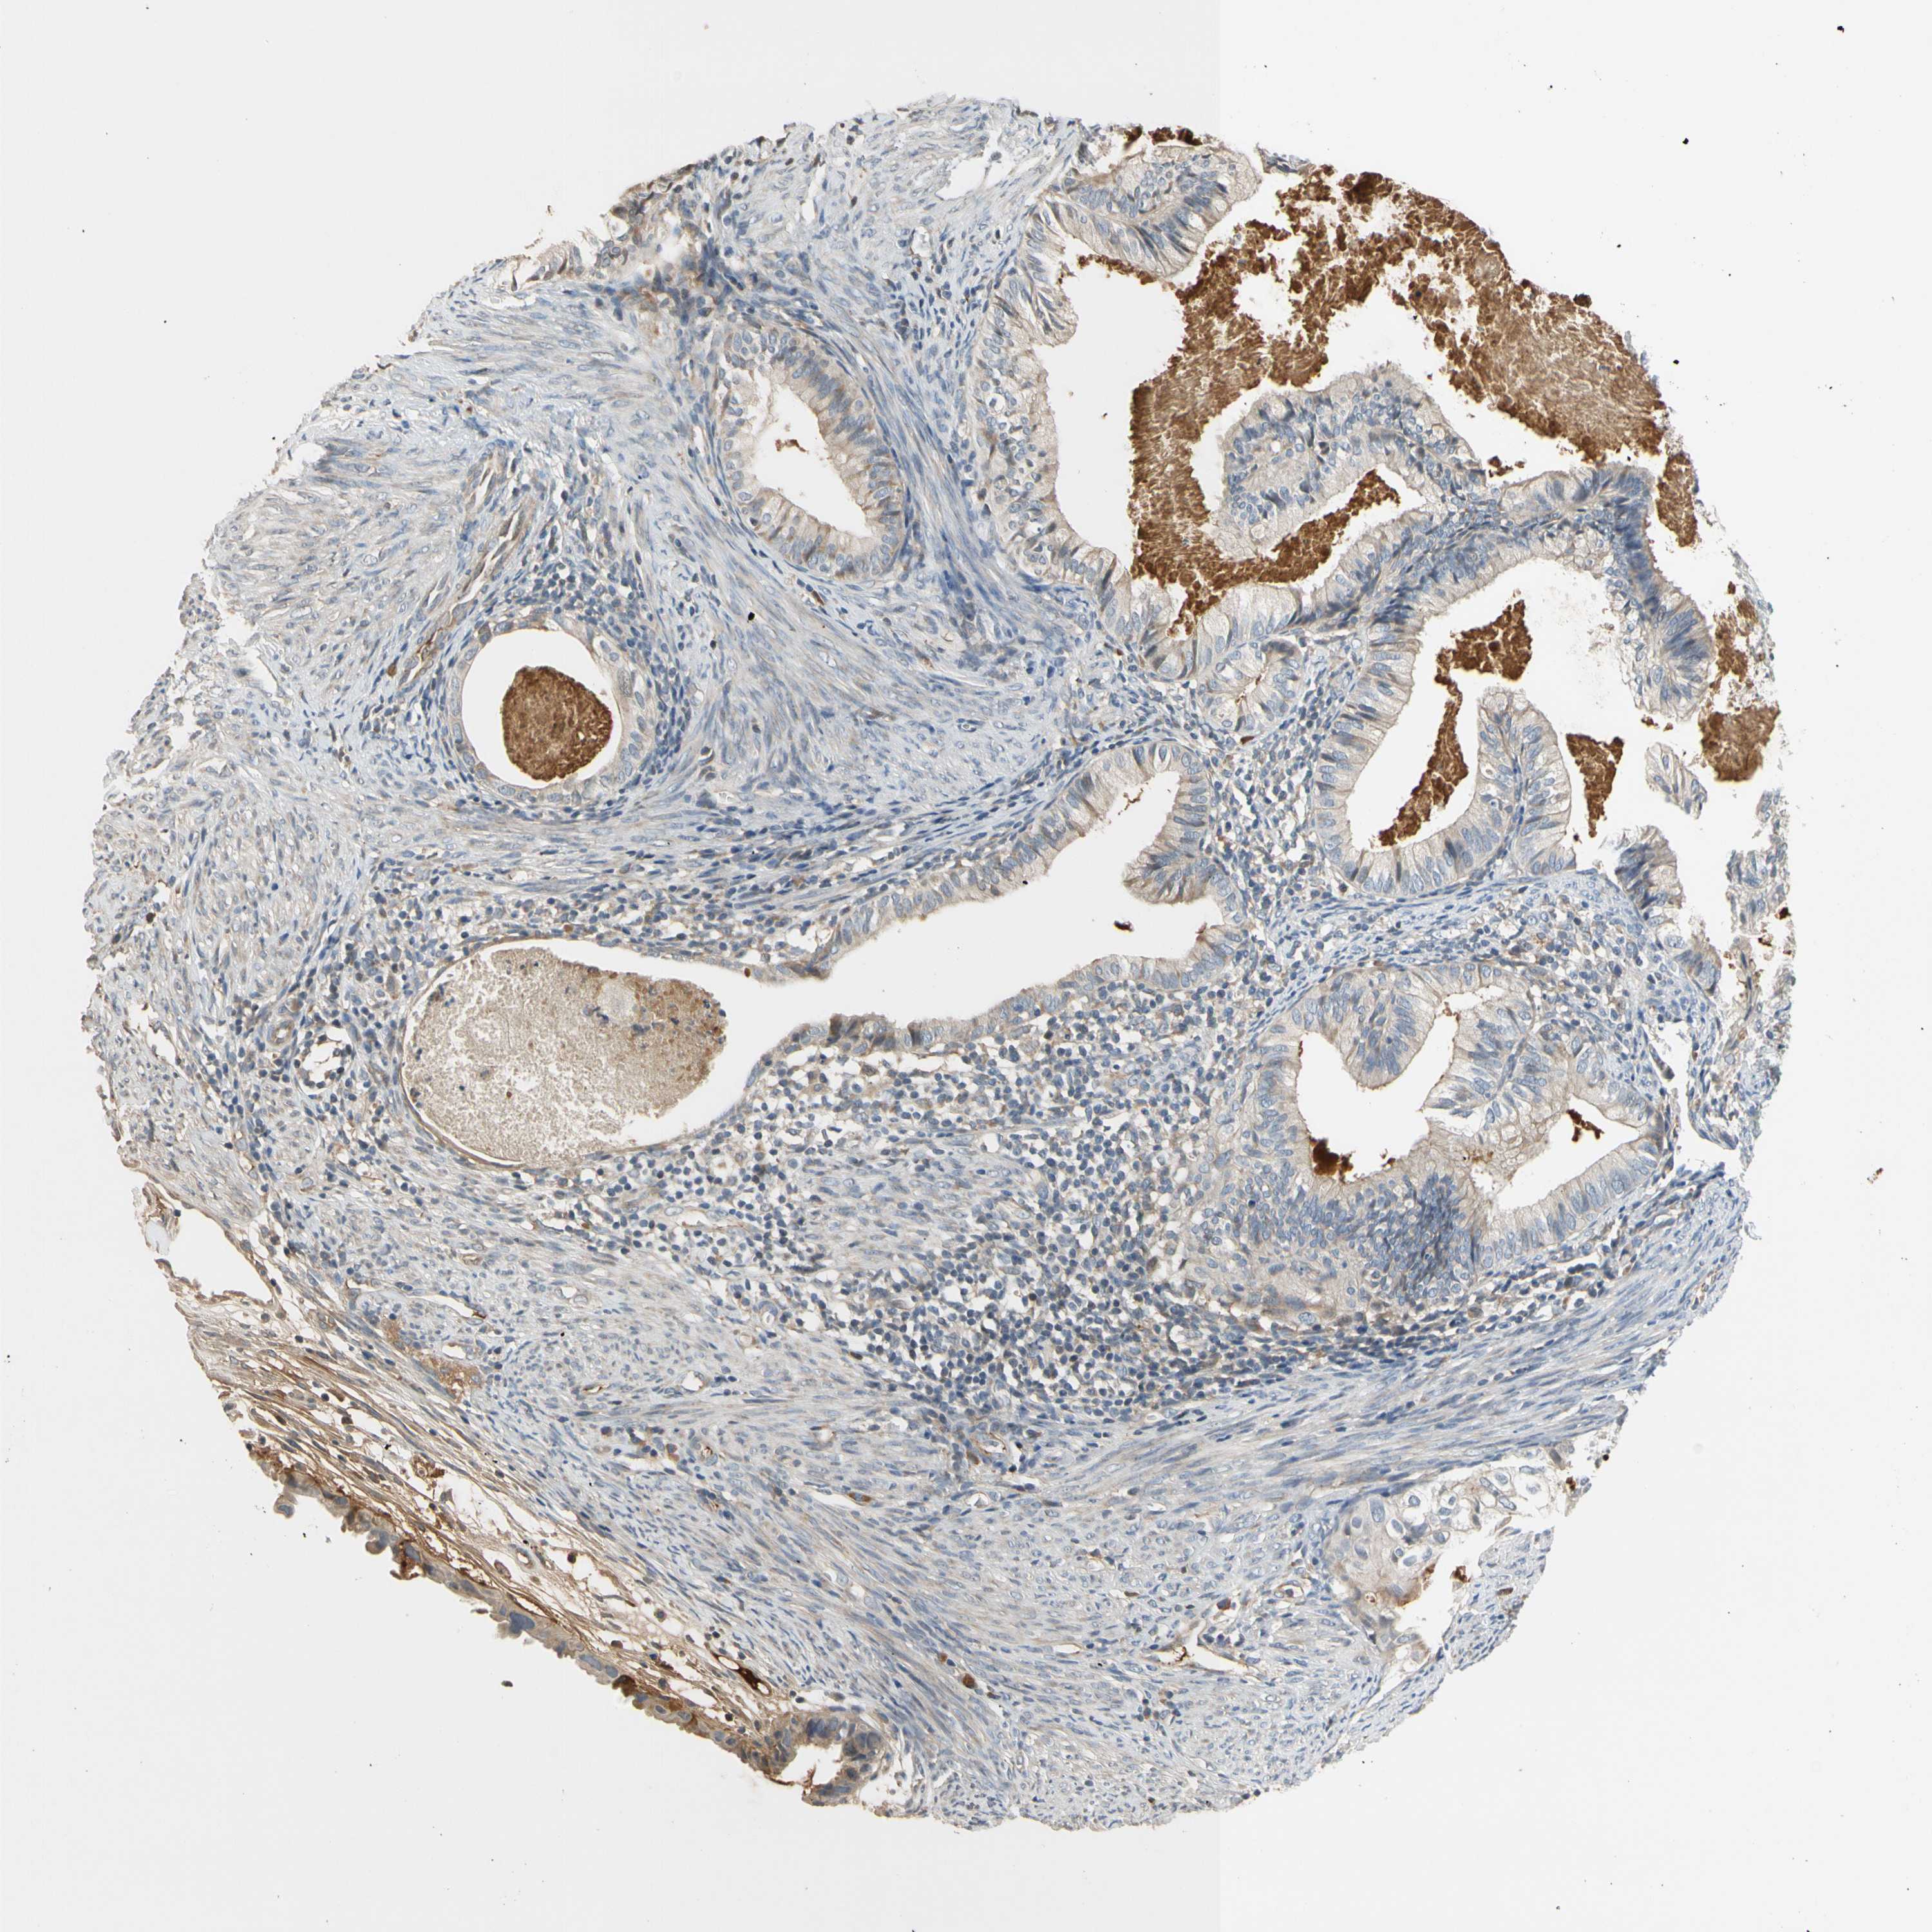

CERVICAL CANCER - Protein expressioni

A mouse-over function shows sample information and annotation data. Click on an image to view it in a full screen mode. Samples can be filtered based on level of antibody staining by selecting one or several of the following categories: high, medium, low and not detected. The assay and annotation is described here.

Note that samples used for immunohistochemistry by the Human Protein Atlas do not correspond to samples in the TCGA dataset.

Antibody stainingi

Antibody staining in the annotated cell types in the current human tissue is reported as not detected, low, medium, or high, based on conventional immunohistochemistry profiling in selected tissues. This score is based on the combination of the staining intensity and fraction of stained cells.

Each image is clickable and will lead to virtual microscopy that enables deeper exploration of all samples and also displays staining intensity scores, fraction scores and subcellular localization as well as patient and tissue information for each sample.

HPA046356

HPA048287

HPA050103

CAB009811

CAB032603

Staining

High

Medium

Low

Not detected

Intensity

Strong

Moderate

Weak

Negative

Quantity

>75%

75%-25%

<25%

None

Location

Nuclear

Cytoplasmic/membranous

Cytoplasmic/membranous,nuclear

Squamous cell carcinoma, NOS

Adenocarcinoma, NOS